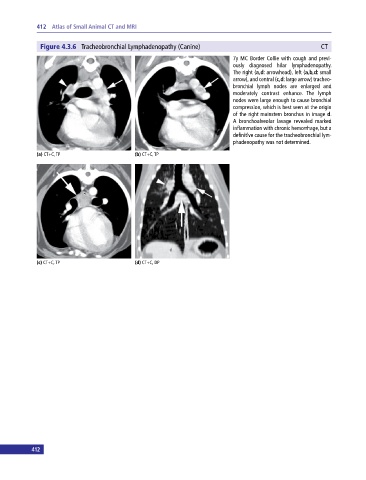

Figure 4.3.6 Tracheobronchial Lymphadenopathy (Canine) CT

7y MC Border Collie with cough and previ

ously diagnosed hilar lymphadenopathy.

The right (a,d: arrowhead), left (a,b,d: small

arrow), and central (c,d: large arrow) tracheo

bronchial lymph nodes are enlarged and

moderately contrast enhance. The lymph

nodes were large enough to cause bronchial

compression, which is best seen at the origin

of the right mainstem bronchus in image d.

A bronchoalveolar lavage revealed marked

inflammation with chronic hemorrhage, but a

definitive cause for the tracheobronchial lym

phadenopathy was not determined.

(a) CT+C, TP (b) CT+C, TP

(c) CT+C, TP (d) CT+C, DP